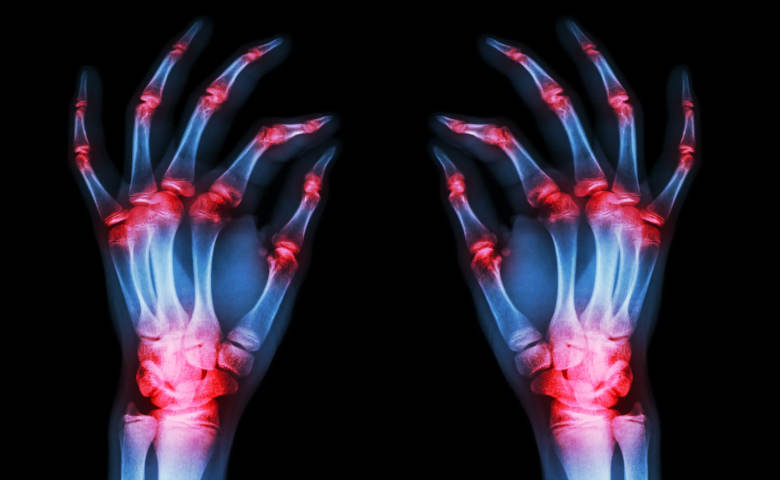

Η αρθρίτιδα είναι φλεγμονή που προσβάλλει τις αρθρώσεις, μια νόσος που δεν θεραπεύεται εντελώς, αλλά μπορεί μόνο να ελεγχθεί η εξέλιξή της, με τη μείωση των συμπτωμάτων, που είναι επώδυνα, και τη βελτίωση, στο μέγιστο δυνατόν, της λειτουργικότητας των αρθρώσεων. Τα πιο κοινά συμπτώματά της είναι: πρήξιμο και δυσκαμψία αρθρώσεων, πόνος, ερεθισμός, κάψιμο στις αρθρώσεις.

Είναι μια αυτοάνοση ασθένεια – προκαλείται από το ανοσοποιητικό σύστημα του οργανισμού – με διάφορες παραλλαγές, κατά τις οποίες η φλεγμονή στις αρθρώσεις, επηρεάζει τους ιστούς γύρω από αυτές, και εξελισσόμενη προοδευτικά, οδηγεί σε μειωμένη κινητικότητα και παραμόρφωση των αρθρώσεων. Η ρευματοειδής αρθρίτιδα σχετίζεται, επίσης, με αυξημένο κίνδυνο λοιμώξεων οστεοπόρωσης – λέπτυνσης των οστών – και αθηροσκλήρωσης – σκλήρυνσης των αρτηριών.